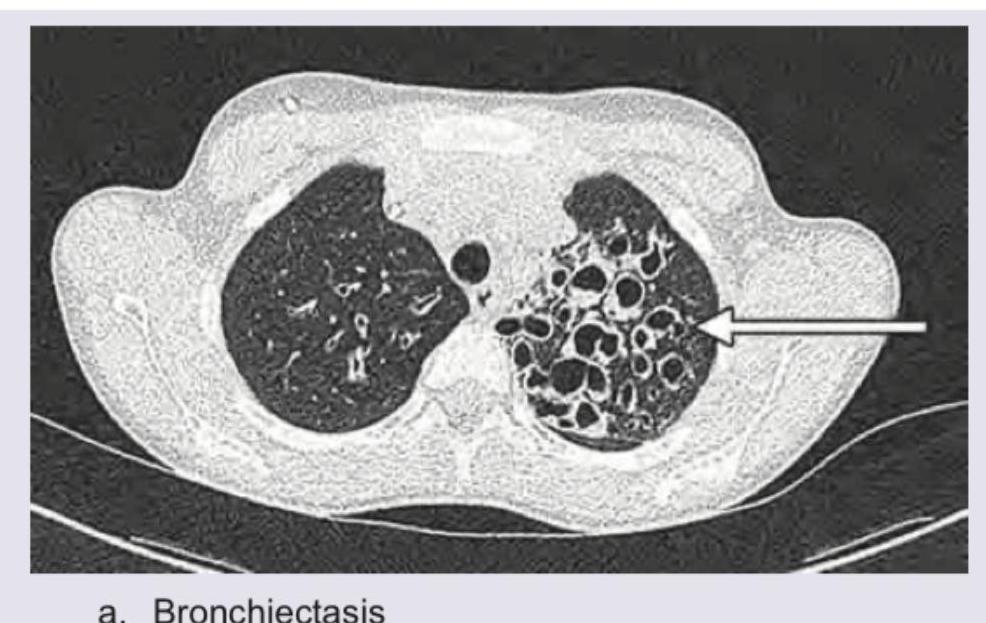

Question 20: The CT chest of a patient given below shows presence of: (Recent NEET Pattern 2016-17)

- A. Bronchiectasis (Correct Answer)

Explanation: ***Bronchiectasis*** - The CT image shows a cluster of **dilated, thick-walled bronchi** in the left lung, which are characteristic findings of bronchiectasis, especially when they are larger than adjacent pulmonary arteries. - The arrow specifically points to these abnormal, saccular dilations of the bronchi, often described as a **"cluster of grapes"** or **cystic appearance**. *Pneumatoceles* - **Pneumatoceles** are typically thin-walled, air-filled cysts that develop as a complication of pneumonia or trauma, and are usually solitary or few in number, not a widespread cluster of dilated airways. - They also often resolve spontaneously, unlike the chronic, irreversible bronchial dilation seen in the image. *Normal scan* - A **normal CT chest scan** would show finely branching airways that progressively narrow as they extend peripherally, without the presence of prominent thick-walled, dilated bronchi or cystic changes. - The image clearly depicts significant structural abnormalities in the left lung making a normal scan highly improbable. *Loculated empyema* - A **loculated empyema** would appear as a collection of pus within the pleural space, characterized by **fluid attenuation**, internal septations, and enhancement of the pleura. - None of these features are the primary findings seen in this image, which shows dilated airways rather than pleural fluid collections.